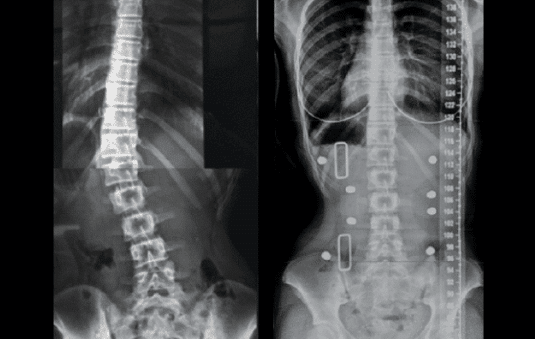

Unlike traditional bracing approaches, the ScoliBrace‘s over-corrective approach and asymmetrical design harnesses spinal coupling, not 3 point pressure, individualizing the correction to achieve an improved alignment of the spine and body posture in the brace.

It ideally achieves an overcorrection or mirror image position of the three-dimensional posture of the body. By achieving this 3D overcorrection, it puts a spine with scoliosis in the straightest possible position.